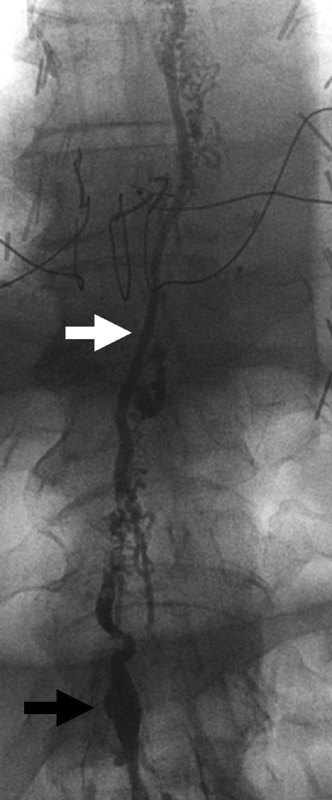

Fig. 4.

Radiograph of central lymphatics during lymphangiography reveals a saccular structure at the bottom of the image (black arrow) representing the cisterna chyli, which gives rise to a single main thoracic duct (white arrow), which crosses from right to left as it ascends toward the neck.

After collecting in the cisterna chyli, lymph flows proximally through the thoracic duct, and ultimately empties in the venous circulation at the junction of the left internal jugular and subclavian veins. Like much of the lymphatics, there are many anatomical variants for both the course and the ultimate destination of the thoracic duct. As the largest lymphatic vessel in the body, the thoracic duct is the major lymphatic-venous connection, returning much of the lymph into the systemic circulation.

The thoracic duct begins at the superior aspect of the cisterna chyli and travels cephalad ( Fig. 4 ). It ascends between the aorta and azygos vein laterally, immediately passing through the aortic hiatus of the diaphragm at the T12 level. As it travels through the posterior mediastinum, the thoracic duct remains anterior to the thoracic vertebrate and intercostal arteries, while staying posterior to the esophagus and pericardium on the right. At the T5 level, it crosses to the left side of the thorax, then running posteriorly to the aorta and subsequent common carotid. The thoracic duct continues to ascend until the C7 level, at which point it descends toward the subclavian and terminates in the venous circulation ( Fig. 5 ).